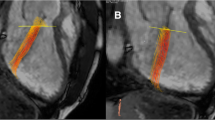

All images (CMR, CT and TTE) were analyzed by one observer (A.T.),who had 6 years of experience in cardiovascular imaging, in a random order and blinded to the results of the other image modalities. The TTE, CT, and CMR data was then re-measured by a second observer (S.Y.), who has one year of experience, blinded to the results of the first observer and to the corresponding measurements of the other modalities. For 2D TTE, speckle tracking analysis was performed using dedicated commercially available software (2D Cardiac Performance Analysis, Tomtec Imaging Systems). End-systolic and end-diastolic frames were identified manually; additionally the annulus and apex were identified manually in end-systole (Fig. 1). Subsequently, the software semi-automatically detected the end-diastolic and end-systolic myocardial contours. These contours were visually checked and corrected if necessary. This process was performed in all apical views (A2ch, A3ch, and A4ch).

Left ventricular parameters by three different modalities in the same patient. TTE Transthoracic Echocardiography, CT Computed Tomography, CMR Cardiovascular Magnetic Resonance, EDV end-diastolic volume, ESV end-systolic volume, EF Ejection Fraction, GLS Global Longitudinal Strain. Yellow lines depict GLS during the cardiac cycle. eS end-systolic phase, eD End-diastolic phase